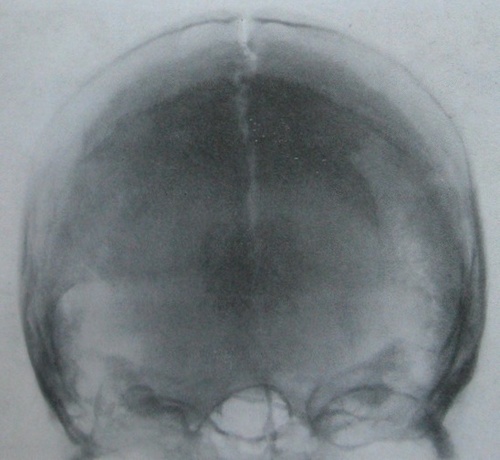

Рентгенография небного шва: Медицинские исследования и диагностика